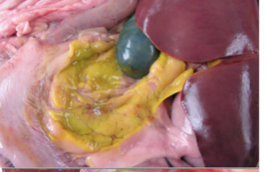

What is occuring in this image? Why?

• Tissues surrounding gallbladder will become stained yellow due to degradation of gall bladder wall.